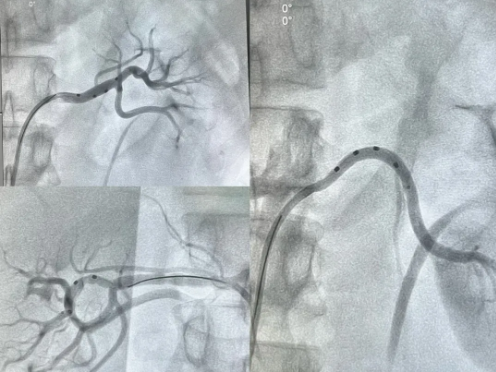

术中,团队将肾动脉消融导管精准送达双侧肾动脉及副肾动脉,运用射频能量对双侧肾动脉交感神经进行消融,累计完成41个位点的消融操作,成功完成手术。术后,在护理团队的精心照料下,患者生命体征保持平稳,现已康复出院。

(术中造影)